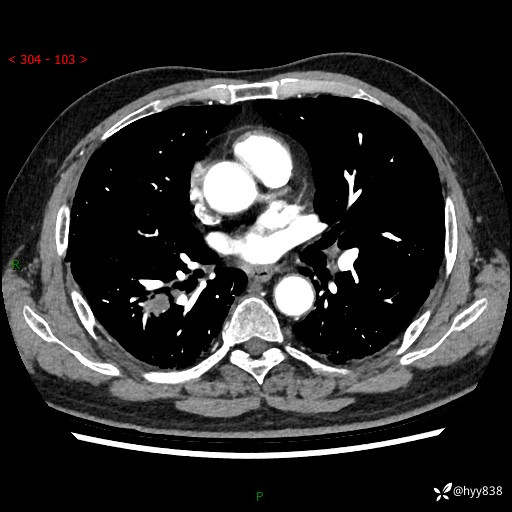

71岁/男,咳嗽伴气促半月。一年前肺手术史,又见两个结节,穿刺结果意外---结果公布~

【现病史】:患者半月前无明显诱因出现咳嗽、咳痰,为白色粘痰,无明显加重与缓解因素,伴气促,无发热,无大量脓痰,无胸痛、咯血,无哮鸣音,到我院就诊,胸部CT示右肺结节增大,并口服药物治疗无明显好转,具体用药不详,为求进一步治疗随来我院,经门诊以“孤立性肺结节”收入我科。 病程中患者精神、饮食可,睡眠不佳,大小便正常,体力下降,体重未见明显下降。

[既往史]:2022-06于当地第一人民医院确诊慢阻肺,现规律使用杰润(1次/日);2023-04-06于当地市第一人民医院行胸腔镜右肺上叶楔形切除术+右肺上叶切除术+淋巴结清扫术+胸膜黏连松解术,确诊为右肺鳞癌 pT2aN0M0 Ib期

【检查】:胸部CT平扫+增强